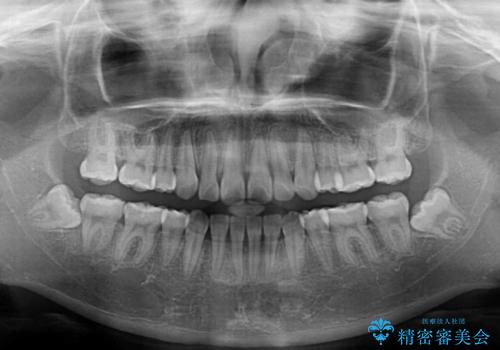

上下の骨格での左右差が小さかったことと、抜歯矯正であったことで、上下正中の位置をきれいに合わせることができました。